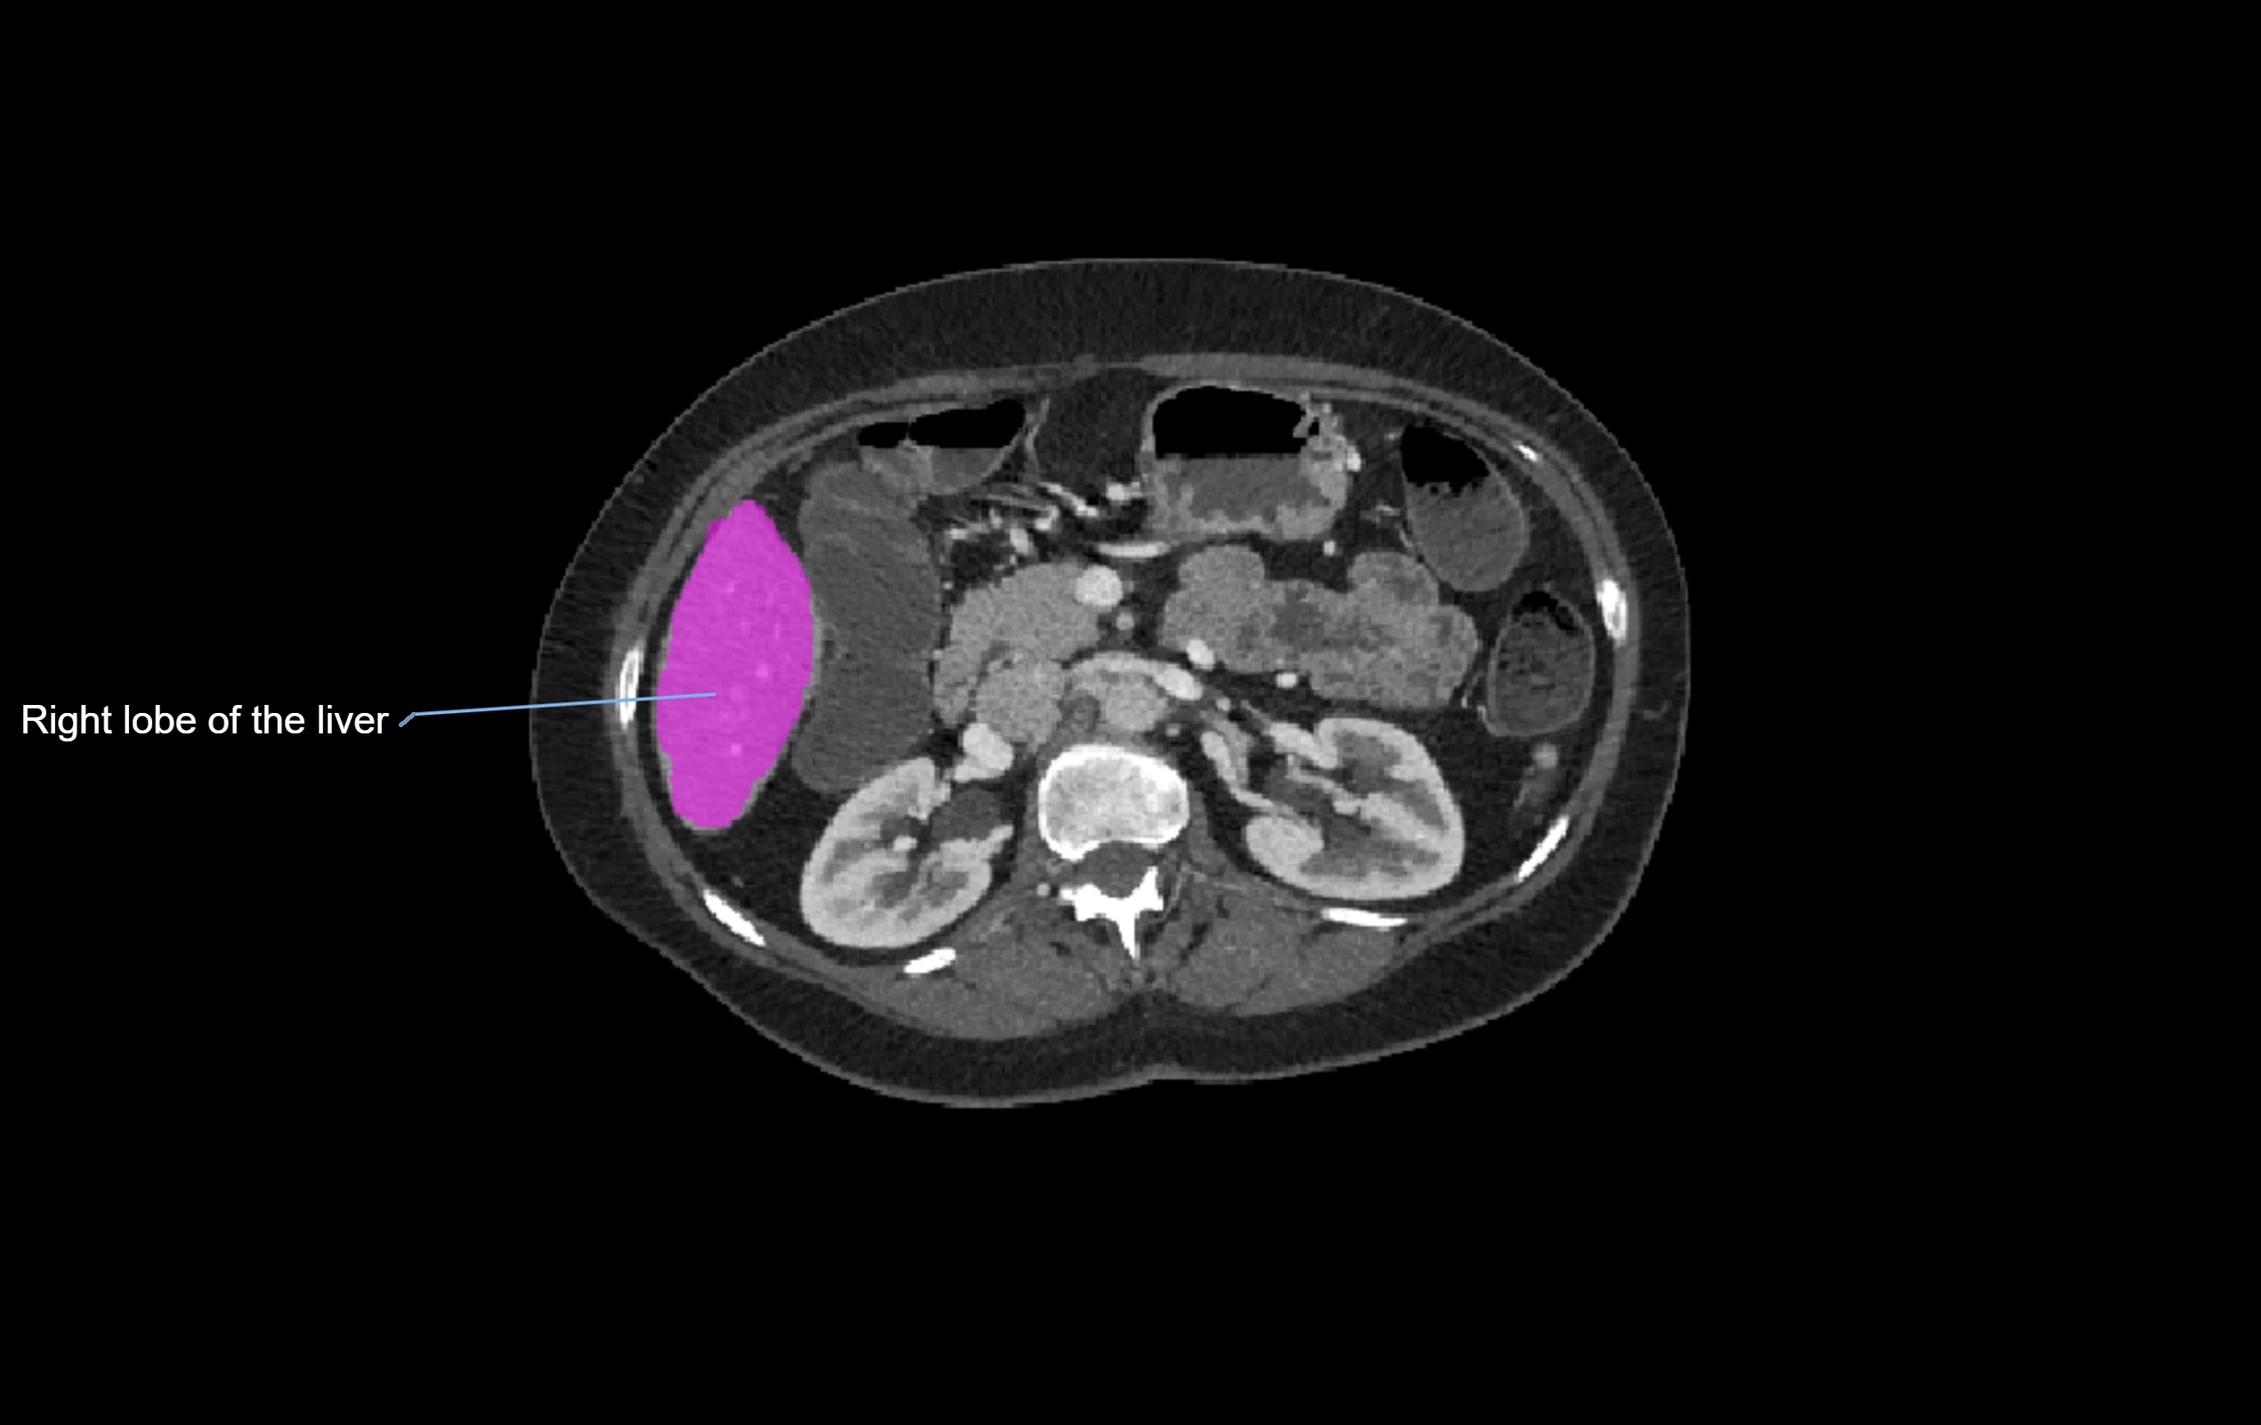

CT Appearance

CT Pre-Contrast:

• Caudate lobe appears as a soft-tissue density, isodense to the rest of the liver

• Enlargement may be appreciated in cirrhosis or Budd–Chiari syndrome